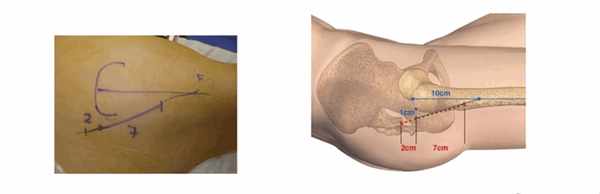

Нанесение ориентиров упрощает выполнение разреза. Верхний бугор большого вертела хорошо пальпируется, когда пациент находится в положении лежа на боку на плоской поверхности. От этого места наносятся две точки: первая на расстоянии 1 см располагается за бугром большого вертела, вторая — на расстоянии 10 см от вершины по оси бедренной кости. По линии, связывающей эти две точки делается разрез: 2 см ниже и 7 см выше от бугра вертела.